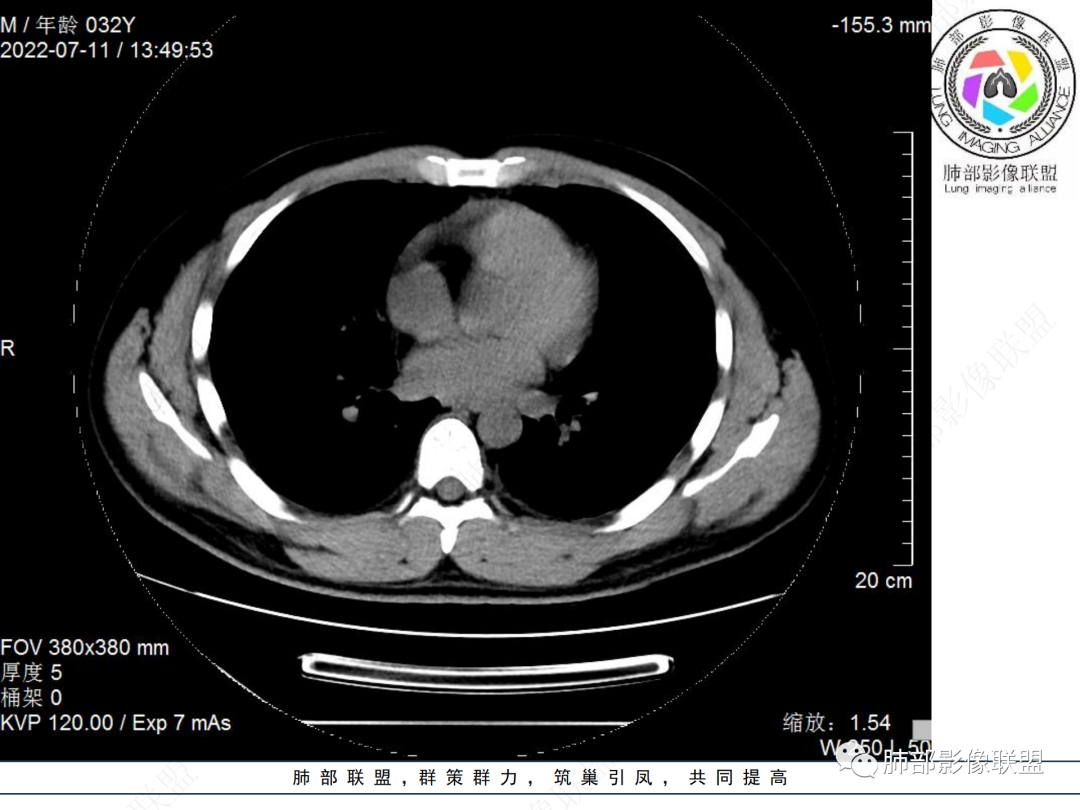

左肺下叶后基底段开口处结节,边缘光滑清楚,没有增强扫描,年轻男性患者痰血三天,考虑1.良性病变:腺瘤、错构瘤、平滑肌瘤

2.恶性:类癌、粘液表皮样癌。

左肺下叶外后基底段气管内见结节状影,边缘部分清晰。考虑错构瘤,待排恶性病变。

左肺下叶气管内外占位病变,咯血病史,考虑类癌,粘表待排。

青年男性,左肺下叶后基底段支气管开口软组织结节,边缘光整,气管镜提示质软,易出血,考虑类癌

左肺下叶后基底段开口处结节,边缘光滑清楚,年轻患者考虑鳞癌或腺样囊腺癌

左肺下叶气道腔内占位,远端无花花草草,疾病谱:鳞,类癌,粘表,腺样囊腺癌,小,无增强,不好判断,临床咯血,选类癌。

大支气管腔内结节,考虑类癌

左肺下叶后基底段开口处结节影,边缘光滑,患者年龄较小,首选类癌

男性,咳血左肺下叶支气管腔内结节影,没有阻塞性炎症,考虑类癌,鳞癌

年轻男性,支气管内结节,首先类癌

左肺下叶后基底段开口处腔内见壁结节,花生米样,宽基底,补充增强及矢状位重建,确定我无向壁外突破浸润生长,另见强化的特点,临床触之易出血,类Ca可能性大。

年轻男性,支气管腔内占位,边缘尚平整,年轻人,首先类癌,鉴别错构

年轻男性,咳血,左肺下叶后基底段支气管腔内结节,边缘光滑,首先考虑青年三件套,类癌大于粘液表皮样癌,支气管镜质软,触之易出血,鉴别血管瘤,平滑肌瘤

左肺下叶后基底段开口部结节,密度较均匀一致,边缘较光整,目测密度偏低,支气管镜示:质软、触之易出血,考虑恶性,类癌。

支气管腔内结节,有蒂与支气管壁连接,考虑良性病变可能性大,支气管错构瘤  血管瘤一类的

左肺下叶后基底段支气管腔内结节,有蒂,容易出血,先考虑良性病变,肉芽组织型血管瘤,与类癌鉴别。

青年男性,左肺下叶后基底段支气管开口软组织结节,边缘光整,气管镜提示质软,易出血,考虑恶性类癌

左肺下叶后基底段开口处结节影,边缘光整,年轻患者,伴咯血,考虑鳞癌,类癌不能排除